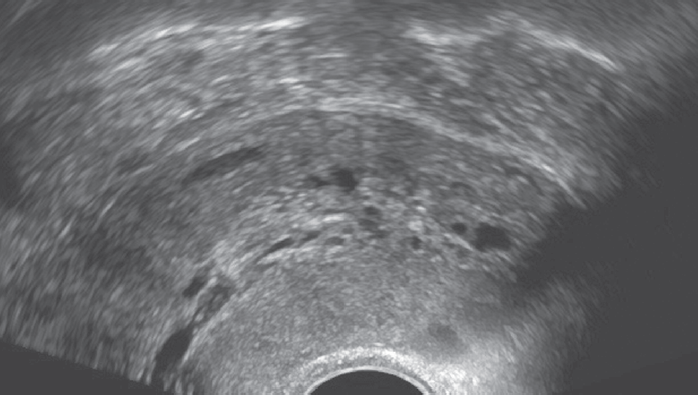

Если методом УЗИ выявлены увеличение толщины эндометрия > 11 мм, усиление васкуляризации, неоднородность структуры, наличие жидкости в полости матки у бессимптомных больных, необходимо отразить данные признаки в протоколе и согласовать с онкологом дальнейший объем обследования пациентки (рис. 3). На первом этапе в этих случаях показана аспирационная биопсия эндометрия. При цитологических признаках гиперплазии эндометрия без атипии (независимо от возраста больных) показаний для гистероскопии с биопсией и/или с фракционированным кюретажем нет. Целесообразно продолжить терапию тамоксифеном и проводить динамическое УЗИ-наблюдение.

Рис. 3. Пациентка К. Постменопауза 8 лет. Прием тамоксифена — 5 лет. Увеличение толщины эндометрия до 18 мм

Fig. 3. Patient K., 8 years postmenopausal, after 5 years of Tamoxifen therapy. Endometrial thickness is increased to 18 mm